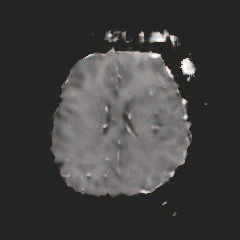

Multi-modal medical image completion has been extensively applied to alleviate the missing modality issue in a wealth of multi-modal diagnostic tasks. However, for most existing synthesis methods, their inferences of missing modalities can collapse into a deterministic mapping from the available ones, ignoring the uncertainties inherent in the cross-modal relationships. Here, we propose the Unified Multi-Modal Conditional Score-based Generative Model (UMM-CSGM) to take advantage of Score-based Generative Model (SGM) in modeling and stochastically sampling a target probability distribution, and further extend SGM to cross-modal conditional synthesis for various missing-modality configurations in a unified framework. Specifically, UMM-CSGM employs a novel multi-in multi-out Conditional Score Network (mm-CSN) to learn a comprehensive set of cross-modal conditional distributions via conditional diffusion and reverse generation in the complete modality space. In this way, the generation process can be accurately conditioned by all available information, and can fit all possible configurations of missing modalities in a single network. Experiments on BraTS19 dataset show that the UMM-CSGM can more reliably synthesize the heterogeneous enhancement and irregular area in tumor-induced lesions for any missing modalities.